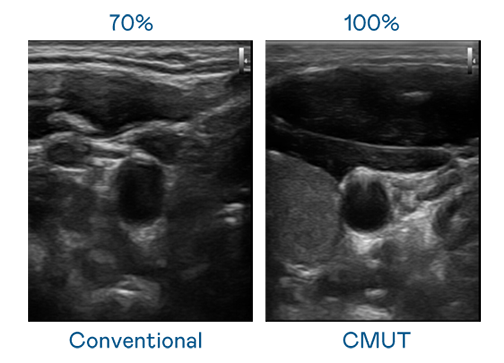

CMUT 技术是一种用电容式微机电元件来产生超音波讯号的技术。与传统 PZT 压电式技术相比,CMUT 频宽增加 30%,更宽频的超音波讯号让影像解析度大幅提升,是实现高影像品质医疗超音波扫描、促进精准医疗发展的关键技术。

大频宽带来超清晰影像

超音波影像的解析度高低,首先取决于探头能发出的讯号频宽。乐鱼leyu官方 CMUT 可提供高清晰的超音波讯号,提供高频宽、高灵敏度、影像纹理细节更高的超音波影像,协助医护人员缩短影像判读时间及利用精准的医疗影像进行诊断。